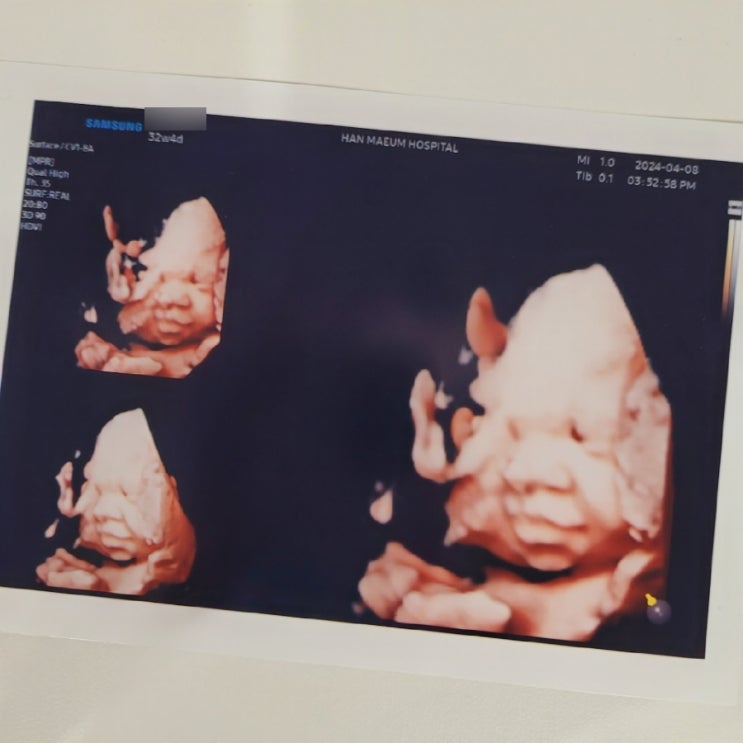

임신 32주 4일 초음파 창원한마음 전자간증 임신중독증 검사 / 가려움증 약처방

임신 32주 4일 초음파 진료 2024. 4. 8 월요일 남편이 일찍 퇴근했던날~ 함께 창원한마음 산부인과 고고씽!...